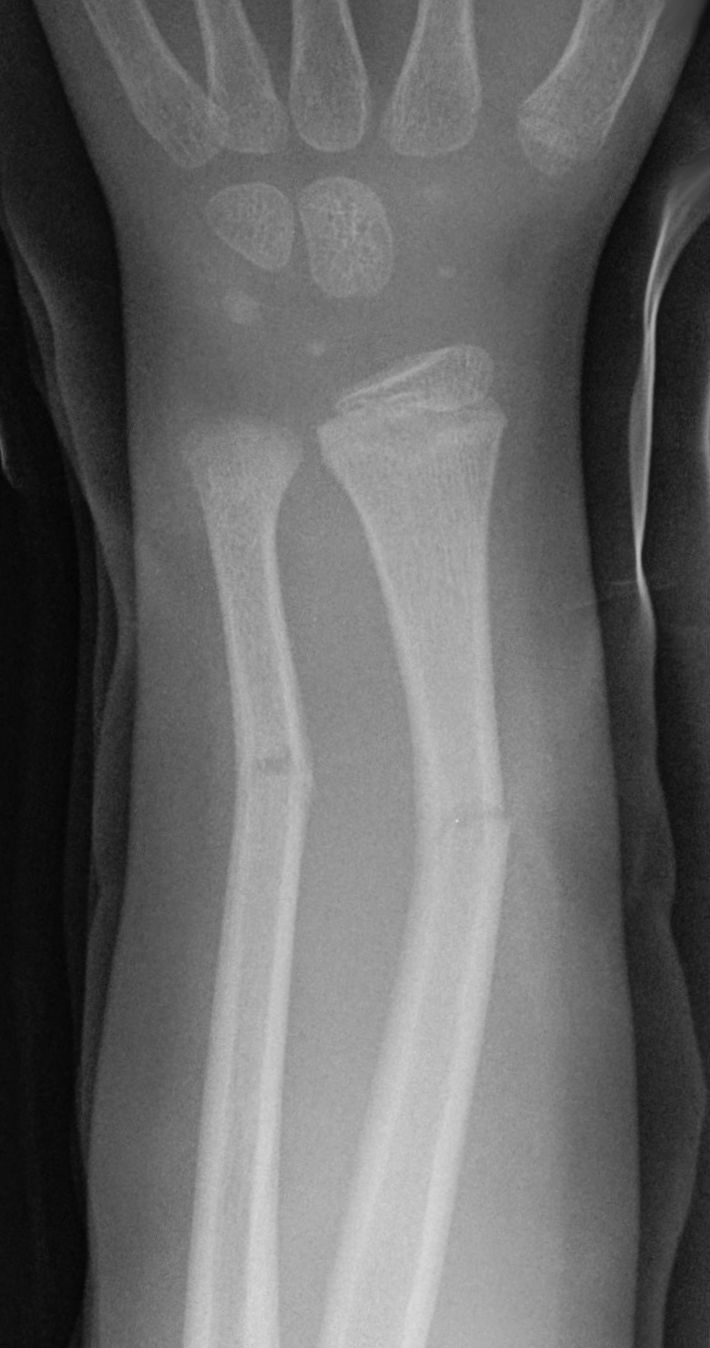

What type of fracture is this? What patient group is often seen in? What type of force causes it?

Torus fracture, also known as buckle fracture → incomplete fracture of shaft of a long bone that is characterised by bulging of cortex. They result from trabecular compression due to an axial loading force along the long axis of bone

children